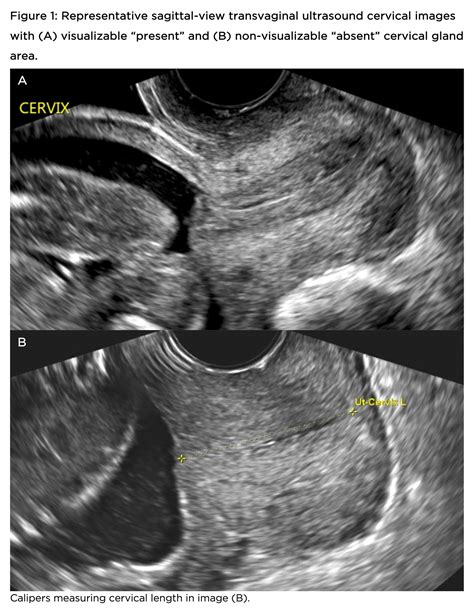

• Transvaginal Ultrasound: This method provides a more accurate measurement of the cervix. A probe is inserted into the vagina to obtain images of the cervix and uterus. This is the preferred method for assessing cervical length, especially during pregnancy.

• normal cervix length ultrasound

• normal cervix length in mm

• normal cervix length during pregnancy